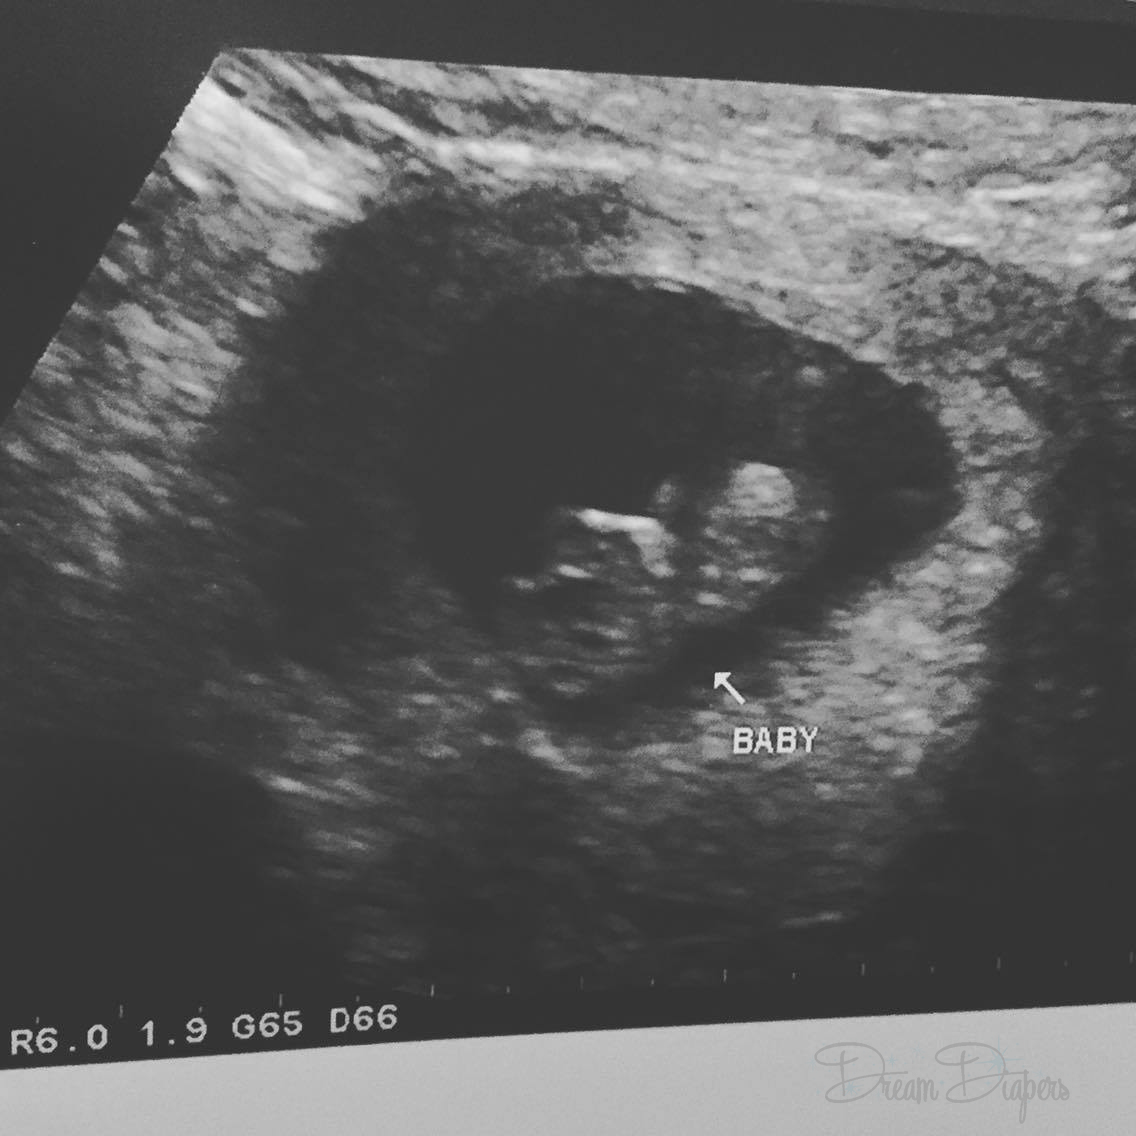

We underwent a procedure called intrauterine insemination (IUI) on December 5th, and a few weeks later discovered that we had finally gotten pregnant. But I was still gone.

Even though I’ve seen the baby on the ultrasound screen three times and heard the heartbeat on two different occasions, I’ve still had a really hard time letting myself be happy and comfortable and secure.